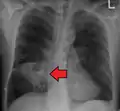

Lung abscess

Lung abscesses are often on one side and single involving posterior segments of the upper lobes and the apical segments of the lower lobes as these areas are gravity dependent when lying down. Presence of air-fluid levels implies rupture into the bronchial tree or rarely growth of gas forming organism.